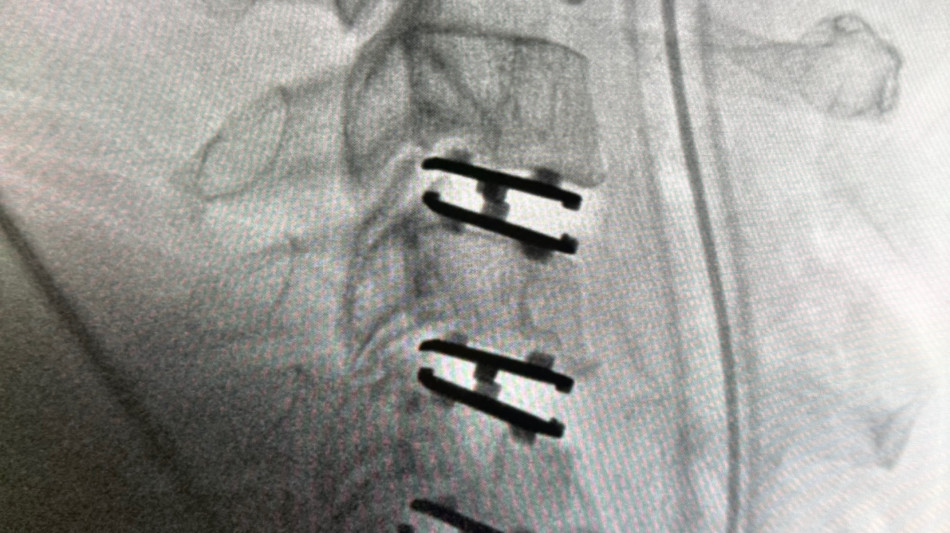

BEVERLY HILLS, CA / ACCESS Newswire / April 8, 2026 / Todd H. Lanman, MD, and Joel S. Beckett, MD have performed the first post-approval case using the newly FDA-approved Synergy Disc®, marking an early clinical milestone for the motion-preserving cervical disc technology.

The procedure was performed on Monday at the Advanced Surgery Center of Beverly Hills five weeks after the U.S. Food and Drug Administration (FDA) granted Premarket Approval (PMA) for the Synergy Disc® for single-level cervical disc replacement from C3-C7.

The patient, a 47-year-old man, presented with progressive neck pain, arm pain, and weakness in the setting of spinal cord compression and severe nerve root compression with associated bone spur formation. After failing conservative management, the patient was taken to surgery for a three-level cervical disc replacement to decompress the spinal cord, relieve nerve compression, and remove osteophytic pathology.

The Synergy Disc® is a motion-preserving artificial cervical disc developed by Synergy Spine Solutions and engineered with a lordotic polyethylene core designed to maintain and restore physiologic alignment while allowing controlled motion. The Synergy Disc® is the only artificial cervical disc currently available that combines motion preservation with intentional alignment correction in a single device. The device recently demonstrated superiority to anterior cervical discectomy and fusion (ACDF) in a U.S. Investigational Device Exemption (IDE) clinical trial.